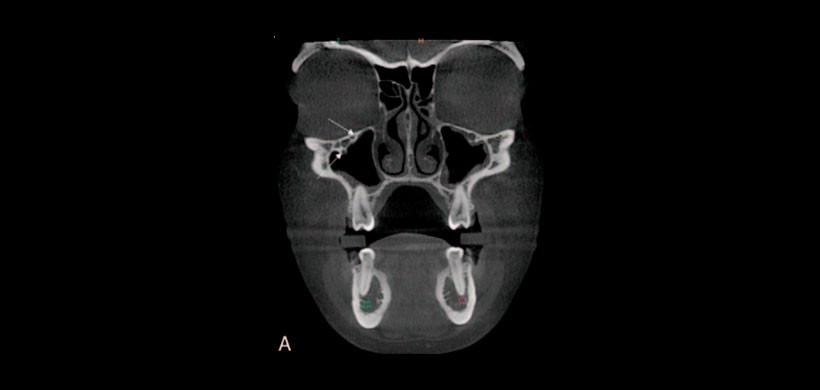

Figura 2: Posición del foramen infraorbitario en relación a la corona de la segunda premolar del maxilar superior

Este estudio está destinado principalmente a evaluar la ubicación y el número de foramen accesorios infraorbitarios (AIOF), para medir la distancia entre foramen infraorbitario principal, AIOF (Figura 1) y secundariamente para determinar la posición del foramen infraorbitario en relación con las coronas del segundo premolar, primer molar y segundo molar del maxilar superior. (Figura 2)

La posición frecuente del foramen infraorbitario se localizó en el eje de la corona del segundo premolar. La presencia de AIOF y la incapacidad de reconocerlo en la evaluación preoperatoria podría considerarse entre las otras razones de falla o anestesia incompleta.